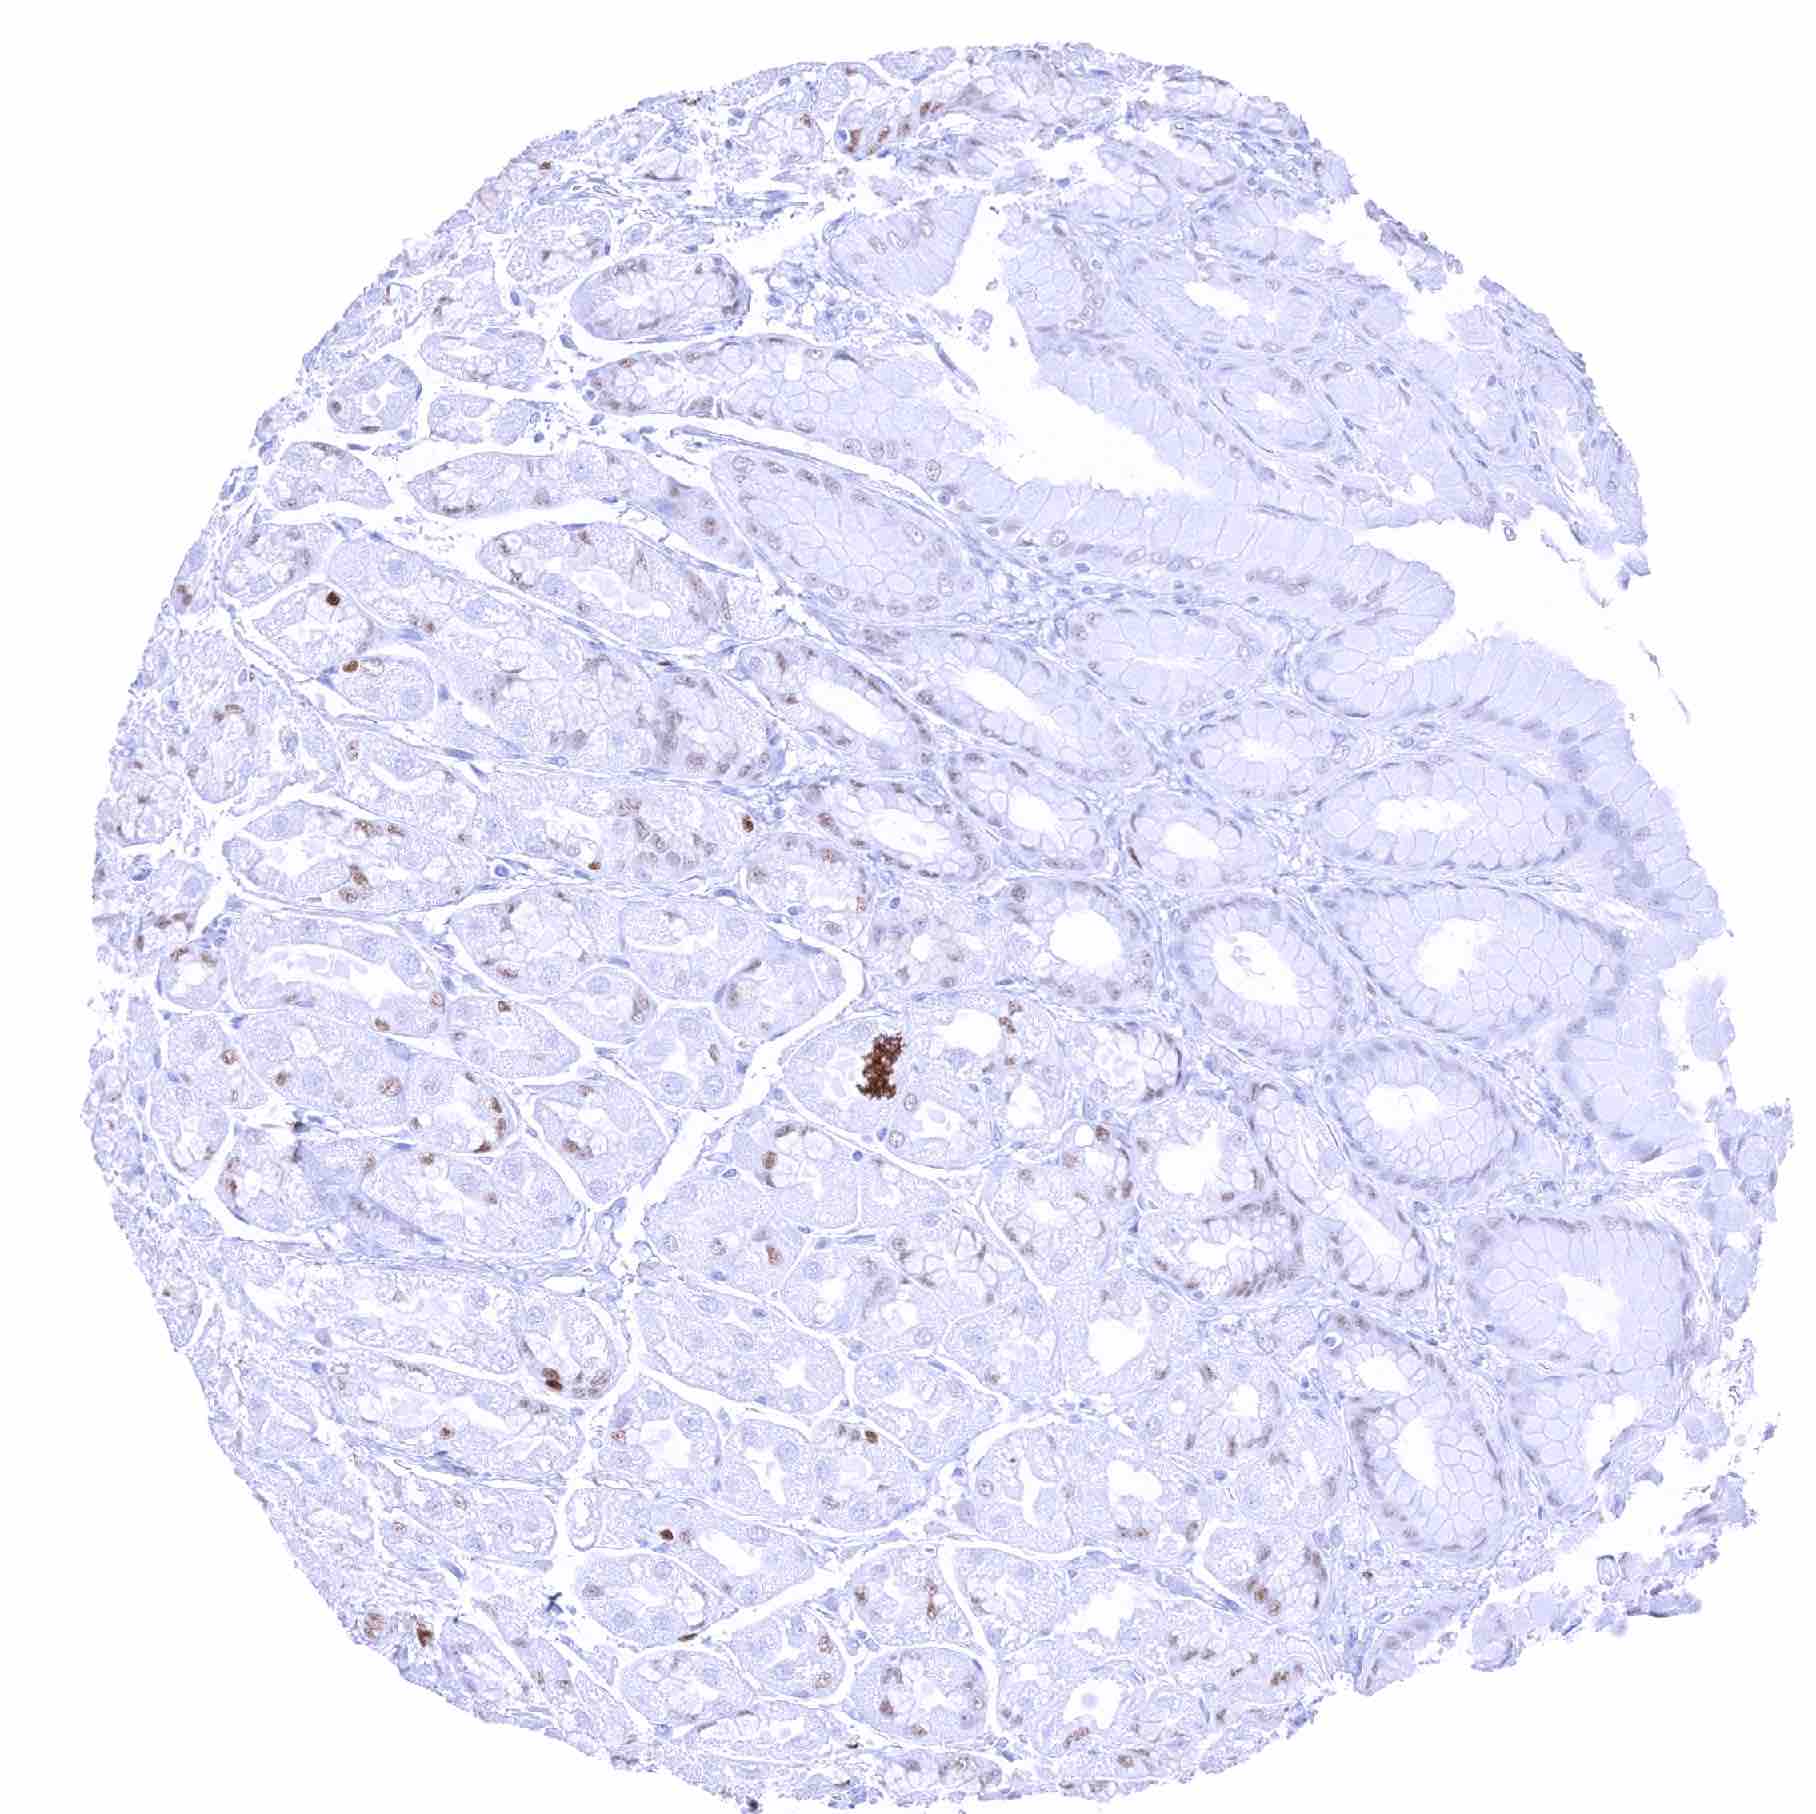

Stomach, antrum – Significant SOX2 staining of a fraction of glandular cells